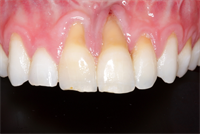

How Do You Know When Your Patient Needs Crown Lengthening?

How do you know when to crown lengthen? In this case, I document the necessary steps to treatment plan and sequence short teeth syndrome cases. Photographs are crucial when making this determination. You can see in the smile shot how short the anterior six appear. They measured about...  Read More